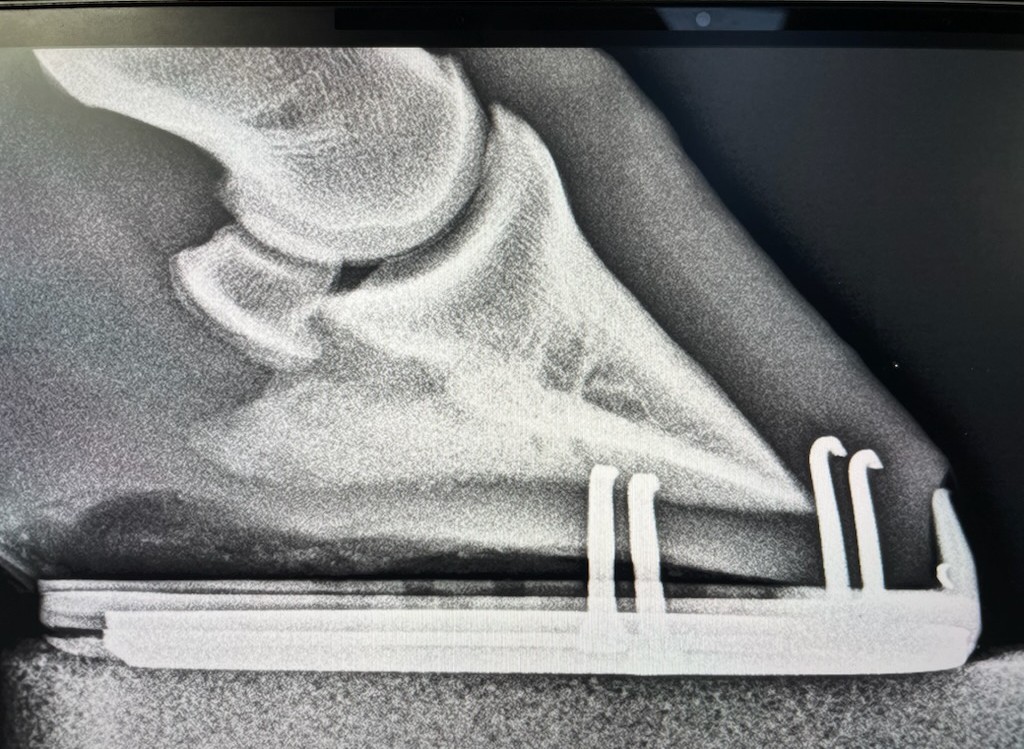

本馬は、自己所有として早期の競走馬デビューを目指し、昨年9月より育成牧場にて調教を進めていたものの、3月に左前肢に原因不明の跛行が見られました。経過を観察しつつ獣医による診察・検査を受けたものの原因が特定されない日々が続きました。今月に入り、再度、レントゲン検査を受けると「左前蹄骨炎」との診断でした。左前の蹄骨の側面に骨瘤のような影があり、跛行の原因との所見を踏まえて検討した結果、早期デビューへの目処が立たないため、このタイミングで所有馬整理の出品とさせて頂きます。母のレイトブルーミングはサラブレッドオークションで落札後、高知で5勝。優秀なファミリーに期待を寄せての産駒だけに残念でなりません。皆様には現状をご理解いただき、ご納得をいただいた上でのご検討、ご入札をお願いし、現状渡しのノークレーム、ノーリターンでお願いいたします。

調教を順調に進めていた段階では坂路で15-15まで乗れていたのですが、原因不明の跛行を見せてからは一進一退が続いている現状です。担当獣医の話では症例が少ないもので競走馬としては五分五分との見解です。装蹄を替えても体重の負重に耐えられなければ装蹄の意味がないですし、経過を見ながら対応していくことだと思います。(加藤ステーブル・加藤天明氏)